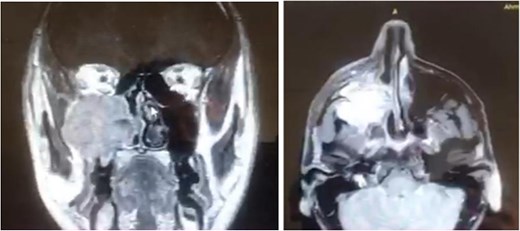

A 42-year-old male previously diagnosed with maxillary nasal sinus squamous cell carcinoma (SCC) was hospitalized for surgical treatment of recurrent infiltrating AC. The patient experienced three recurrences with the initial treatment approach for the cancer as SCC, a non-keratinizing variant. Complete excision and curettage of the lining mucosa were performed. In the second recurrence, the patient underwent additional curettage and subsequently revealed the absence of tumor residues from the mucosa and submucosa. However, the patient experienced a third recurrence with rapid growth and infiltration to the floor of the right maxillary sinus, filling the sinus space, infratemporal fossa, pterygopalatine fossa, cheek buccal area, and orbital floor. The imaging studies were preformed revealing a neoplastic lesion centered on the right maxillary sinus measuring 10 × 5 × 4.5 cm with a low T1 signal, heterogeneous iso T2/STIR signal, and intense heterogeneous post-contrast enhancement (Fig. 1). AC was recognized as stage II based on Yang’s et al. classification system [6]. Right Subtotal maxillectomy was performed through a Weber Ferguson incision with a Dieffenbach extension, and the infiltration areas were cleared. The excised tumor mass from the right maxillary sinus with labeled surgical margins (palate, orbital floor, buccal, and pterygoid surgical margins) was subjected to permanent paraffin evaluation (Fig. 2). The Right hemi-maxillectomy measuring 6 × 4.5 × 4 cm, revealed one canine, two molars, and two premolars found in the alveolar arch. An indefinite, grayish-white, infiltrating, fungating mass, approximately (⁓6 × 4 × 2.5 cm), was observed in the maxillary sinus. The cut surface of the mass was grayish-white and firm, with skeletal muscle attachment and noticeable infiltration into the underlying periosteum of the alveolar arch. Furthermore, labeled tumor tissue fragments measuring 4.7 × 2 × 2.5 cm and multiple smaller pieces collectively measuring 4 × 4 × 2 cm, showing similar characteristics, were stored in the same container. Microscopic examinations were performed at different magnifications. At a low magnification, the specimen revealed the presence of an infiltrative tumor with a biphasic pattern. The Islands and epithelial cell sheets are embedded in the fibrous stroma. The tumor islands exhibited a basaloid appearance with peripheral palisading, reverse polarity, and central stellate reticulum-like cells, reminiscent of ameloblastoma. However, these neoplastic epithelial cells exhibited moderate cytological atypia and increased mitotic activity, which suggests of malignancy (Fig. 3). Higher magnification shows tumor cells with enlarged, pleomorphic nuclei, prominent nucleoli, and eosinophilic cytoplasm. Frequent mitotic figures, including atypical forms, were also observed. Peripherally, tumor islands comprise cells with hyperchromatic elongated nuclei exhibiting focal palisading. The central cells were loosely cohesive and exhibited a stellate reticulum-like morphology. Additionally, focal areas of necrosis, hemorrhage, and keratinization were prominent in the tumor islands, and the surrounding stroma appeared desmoplastic and encompassed moderate chronic inflammatory infiltrates (Fig. 4). Additionally, diffuse infiltration of tumor into the adjacent tissues was observed, including bone and soft tissues, and is associated with perineural and lymphovascular invasion. Tumor extension in the orbital floor and buccal mucosal surgical margins was evident. In contrast, the palatal and pterygoid surgical margins are free of tumor involvement (Fig. 5). Overall, the morphological features were consistent with a diagnosis of infiltrating AC. Furthermore, immunohistochemistry assay was performed using a Ventana BenchMark GX Auto-stainer, employing the Ventana I View DAB detection system and Ventana monoclonal antibodies. The sections were stained for CK 5/6, P63, CK19, SOX-2, SOX-10, calretinin, and Ki67. The results revealed that the tumor basaloid epithelial component was strongly positive for P63 and showed weak heterogeneous positive staining for CK19, calretinin, and SOX-2 (Fig. 6). Conversely, it was negative for CK5/6 and SOX-10 staining. The Ki67 labeled index within the epithelial component was ⁓14%, whereas the mesenchymal component was 8%. The post-operative radiotherapy at 66 Gy was successfully administered. The patient is currently under observation, with careful follow-up.